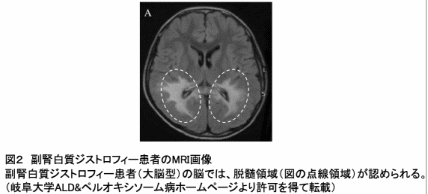

極長鎖脂肪酸は一部の細胞で利用される一方、大部分の細胞では、極長鎖脂肪酸を運ぶ特殊な輸送タンパク質の働きによって分解されます。我が国の難病に指定される副腎白質ジストロフィー(指定難病20)は、この輸送タンパク質の機能が遺伝的に不全であるために生じます。副腎白質ジストロフィーは、脳の中の炎症反応を伴う進行性の脱髄症状※6(図2)や、副腎機能の不全を特徴とする疾患です。